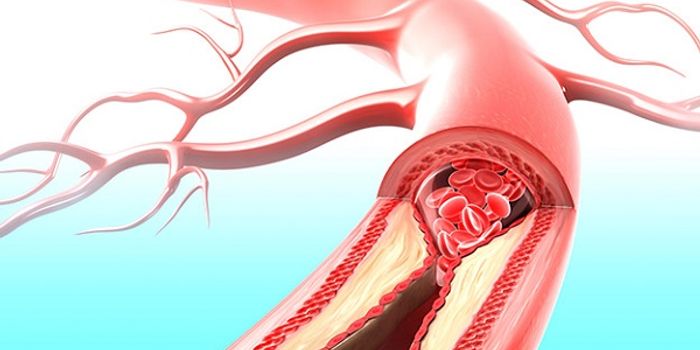

JUN 14, 2016CardiologyMedication to dissolve blood clots and various surgical procedures can be done to reverse damage done to arteries with o ...